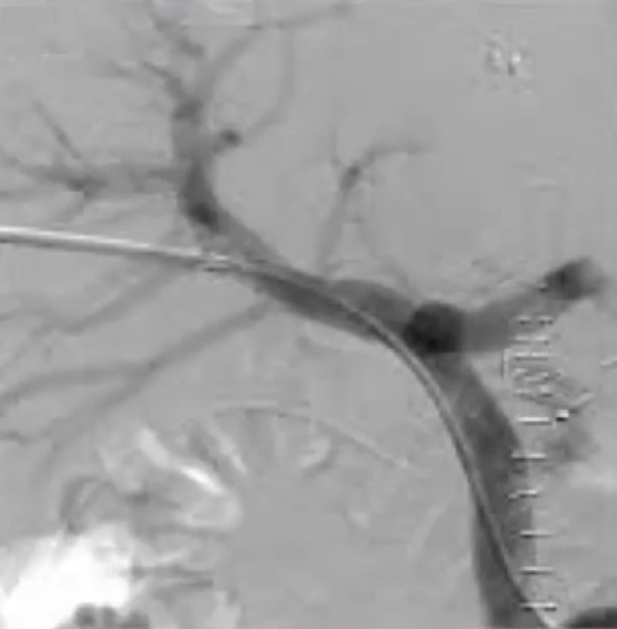

在这种情况下,“Salem ”技术是最佳选择,即进行脾脏穿刺,疏通血栓,放置圈套器,并引导经颈静脉肝内门体分流术(TIPS)操作。

通过经皮经脾路径具有显著优势,能够使用 4Fr 细导管和导丝进行逆向再通操作,以 10 毫米的圈套器作为经颈静脉穿刺目标,通过Avitene 完成经颈静脉门静脉穿刺。